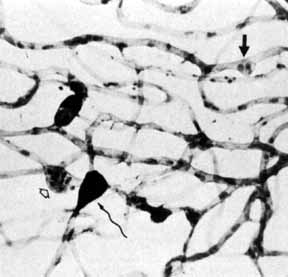

Although microaneurysms are the first ophthalmoscopically detectable change in diabetic retinopathy, the earliest abnormalities seen histopathologically are thickening of the capillary basement membrane1,2 and pericyte dropout.3,4 Pericytes are mesothelial cells that surround and support the retinal capillary endothelial cells. Normally there is one pericyte per endothelial cell. In people with diabetes, however, the pericytes die off and are decreased in number (Fig. 1). Their absence weakens the capillaries and permits thin-walled dilatations, called microaneurysms, to develop. Later, endothelial cells proliferate and lay down layers of basement membrane material. Fibrin may accumulate within the microaneurysm along with erythrocytes, and the lumen of the microaneurysm may become occluded (Fig. 2). Initially, most microaneurysms are on the venous side of the capillaries, but later they are seen on the arterial side as well. Clinically, they appear as small red dots (Fig. 3). Despite the multiple layers of basement membrane, microaneurysms are permeable to water and large molecules, allowing the transudation of fluid and lipid into the retina.

Fig. 2 Trypsin digest preparation of early background retinopathy. Early microaneurysm (closed arrow), aneurysm with endothelial proliferation (open arrow), and aneurysm occluded with fibrin (curved arrow). (Courtesy of Dr. Myron Yanoff)